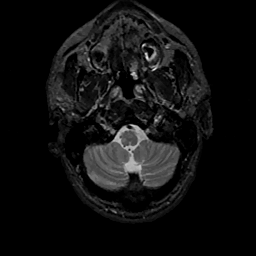

MR Study #11, May 5, 1991 -- Slice #5